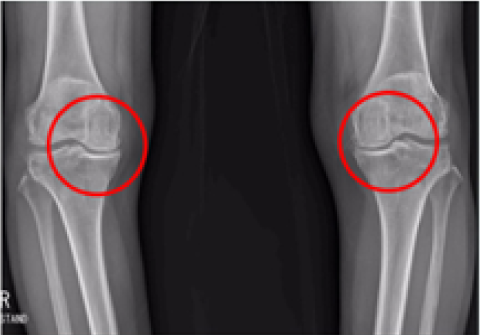

무릎 인공관절 부분치환술

2016.06.27

2016.12.28